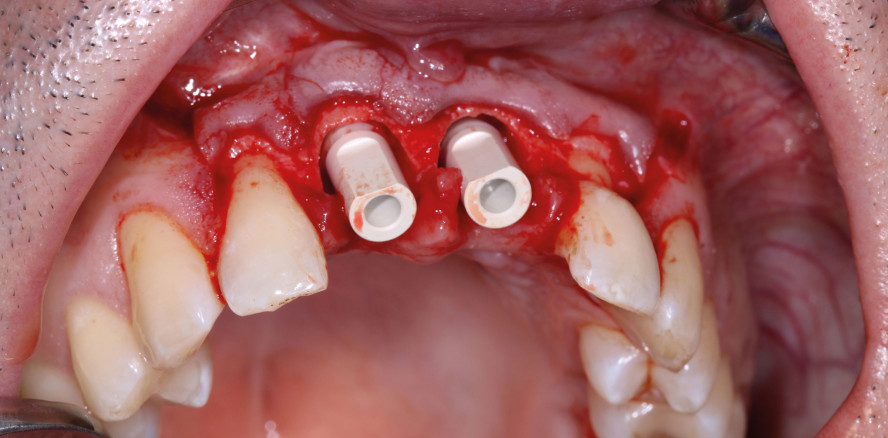

Vor der Operation wurde auf Grundlage von Röntgenaufnahmen (Abb. 1) und einer 3D-Planung (Orthophos SL 3D, Dentsply Sirona) ein Behandlungsplan für die Sofortimplantation mit den zweiteiligen dentalen CERALOG Implantaten erstellt. In einem ersten chirurgischen Schritt wurde ein Lappen angehoben, die beiden Zähne 11 und 21 wurden extrahiert und umfangreiche periapikale Zysten entfernt (Abb. 2–4). Danach wurden sofort zwei Implantate mit einer Länge von 12 mm und einem Durchmesser von 4 mm inseriert (Abb. 5). Anschließend wurde ein optischer Abdruck (CEREC Omnicam, Dentsply Sirona) für die Herstellung von CAD/CAM-gefertigten individuellen Aufbauten genommen (Abb. 6), die nach sechs Monaten bei der Freilegung der Implantate eingesetzt werden sollten. Die zweiteiligen Implantate wurden während des chirurgischen Eingriffs mithilfe eines Geistlich SafeScraper TWIST (Geistlich Pharma; Abb. 7) mit Knochenspänen aus dem posterioren Bereich des Unterkiefers bedeckt. Anschließend wurde die Operationsstelle zur gedeckten Einheilung der Implantate vernäht (Abb. 8). Zudem wurde unmittelbar nach der Operation ein Röntgenbild angefertigt (Abb. 9).